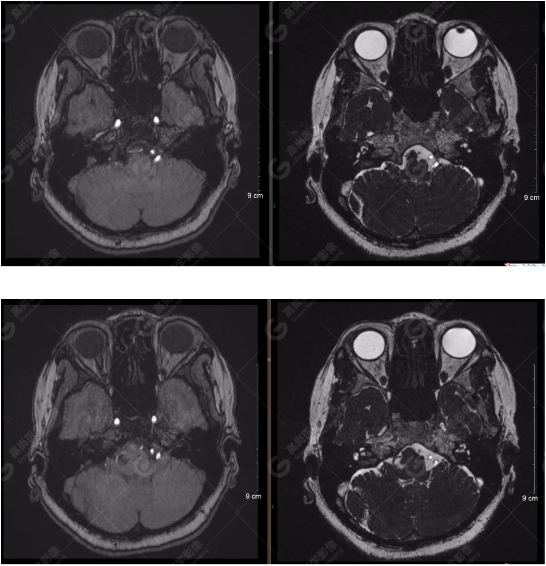

顱腦MRA及ciss序列示腦基底動脈環(huán)完整,雙側(cè)頸內(nèi)動脈末段、大腦前動脈、大腦中動脈、大腦后動脈及其主要分支顯影良好,管徑及走行正常,無明顯局灶性增粗或變細(xì)。雙側(cè)椎動脈末段沿延髓左側(cè)向上走行,左側(cè)面聽神經(jīng)輕度受壓移位,左側(cè)面聽神經(jīng)周圍見細(xì)小血管包繞。右側(cè)面聽神經(jīng)及雙側(cè)三叉神經(jīng)周圍未見異常血管影。

1.雙側(cè)椎動脈末段沿延髓左側(cè)向上走行,左側(cè)面聽神經(jīng)輕度受壓移位,左側(cè)面聽神經(jīng)周圍見細(xì)小血管包繞,可符合面聽神經(jīng)壓迫綜合征。